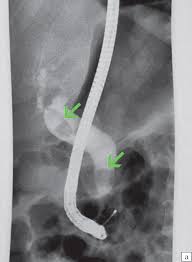

Хворому з жовтяницею для верифікації діагнозу проведено додаткове дослідження. Що за метод додаткового інструментального дослідження зображено на картинці та яка причина жовтяниці?

0%